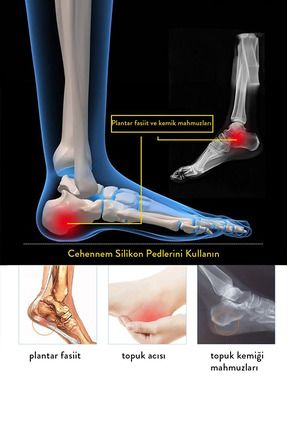

- هدف از استفاده : Topuk Dikeni